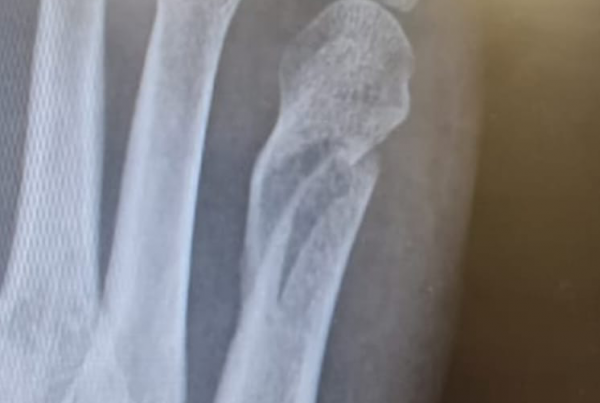

Key facts about osteoporosis: In osteoporosis, the bone struts become thin and susceptible to breakage, resulting in an altered bone structure. This makes the bones more fragile and prone to fractures.